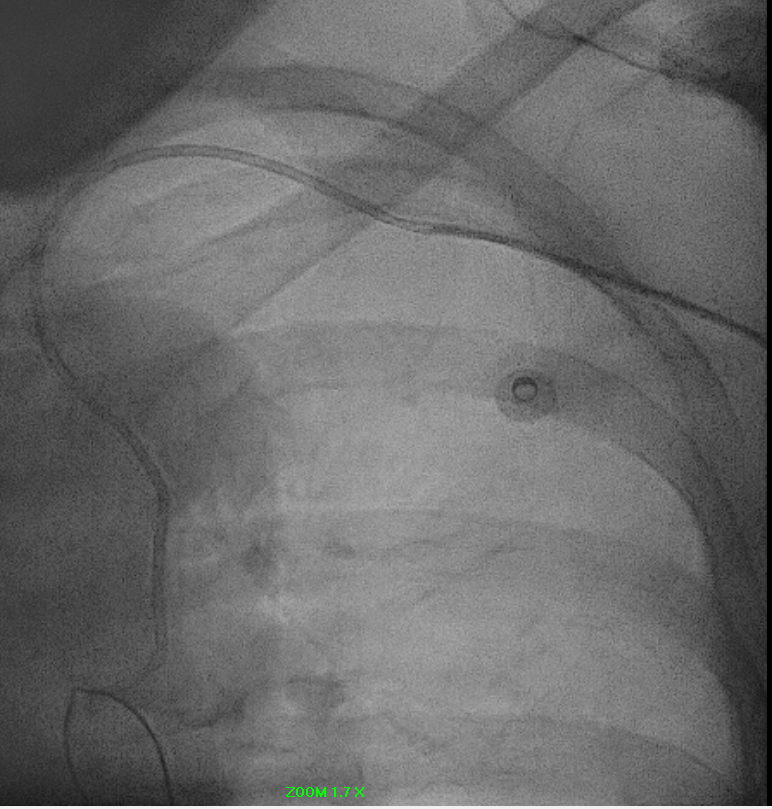

Distal tip of catheter was snared and manage to unkink catheter.

Optitorque 5FR catheter successfully removed from left radial sheath.

Right femoral closed with Perclose Prostyle 6FR.

Patient was observed overnight without any complications and discharged well the following day.